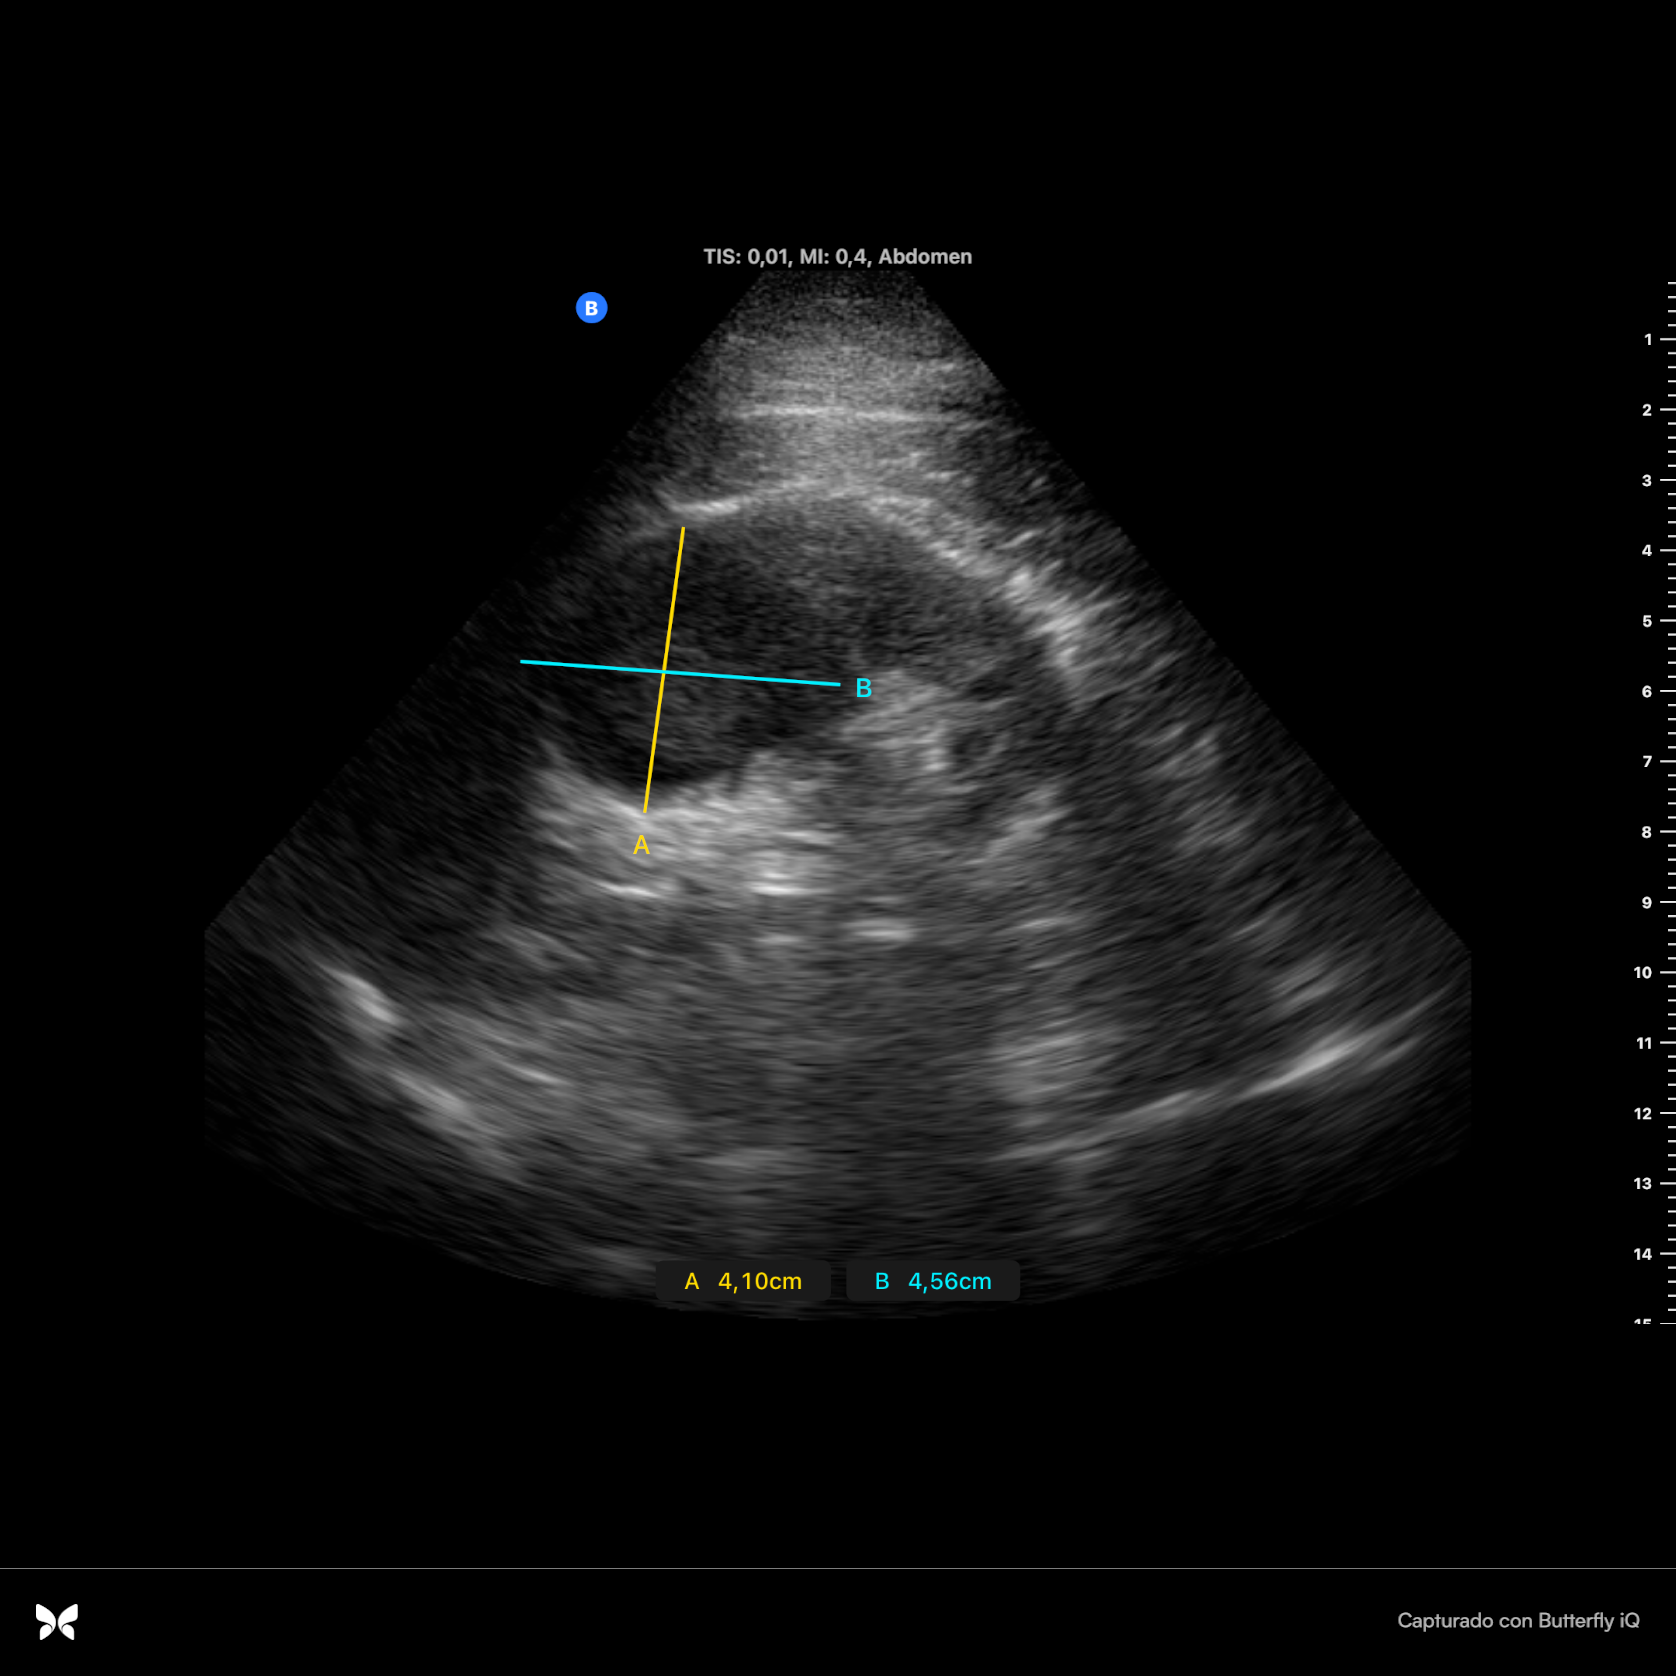

Se realiza con sonda ecográfica portátil. Se inicia el estudio ecográfico del abdomen a nivel de la línea axilar media derecha, donde realizamos cortes longitudinales y transversales. En el riñón derecho se observa, a nivel del polo superior, una lesión sólida heteroecoica, hipoecogénica respecto al parénquima circundante, redondeada, de bordes bien definidos, sin refuerzo posterior (figura 1), de 4,10 x 4,56 cm (figura 2) y con vascularización (Doppler positivo) (figura 3).